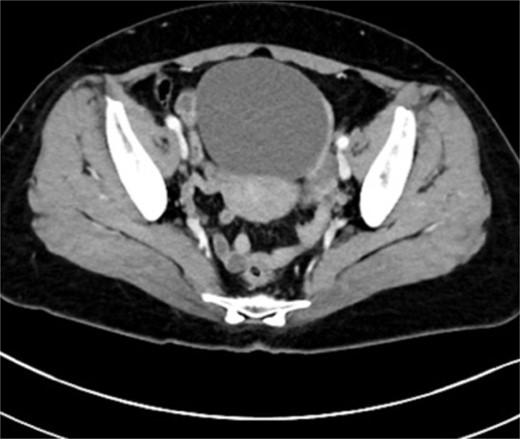

On admission, the patient was found to have a soft tumor, 10 cm in size, in her lower abdomen. She didn’t feel any tenderness at the site of the tumor. Abdominal ultrasonography showed a cystic mass with a small solid portion with a clear margin. Her serum levels of CA125, CA19-9, and carcinoembryonic antigen (CEA) were within normal limits. Computed tomography (CT) scan revealed a 10 cm sized cystic mass (Fig. 1). Magnetic resonance imaging (MRI) also revealed a 10 cm sized cystic mass with a solid part in the pelvis (Fig. 2).

Pelvic computed tomography image: A large mass occupying the pelvis which is a 10 cm sized cystic mass.